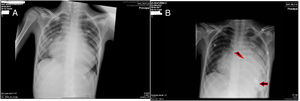

A) Se muestra la Rx de tórax previa al implante de la asistencia ventricular donde se aprecia una importante congestión venocapilar pulmonar secundaria a la grave disfunción del VI. B) Rx de tórax del 3.° día postimplante de la asistencia ventricular donde ha disminuido el componente de congestión venocapilar pulmonar. La flecha señala la posición de la cánula apical implantada en el VI. El símbolo del rayo marca la bioprótesis pulmonar que se identifica por los 3 puntos radioopacos de la misma.